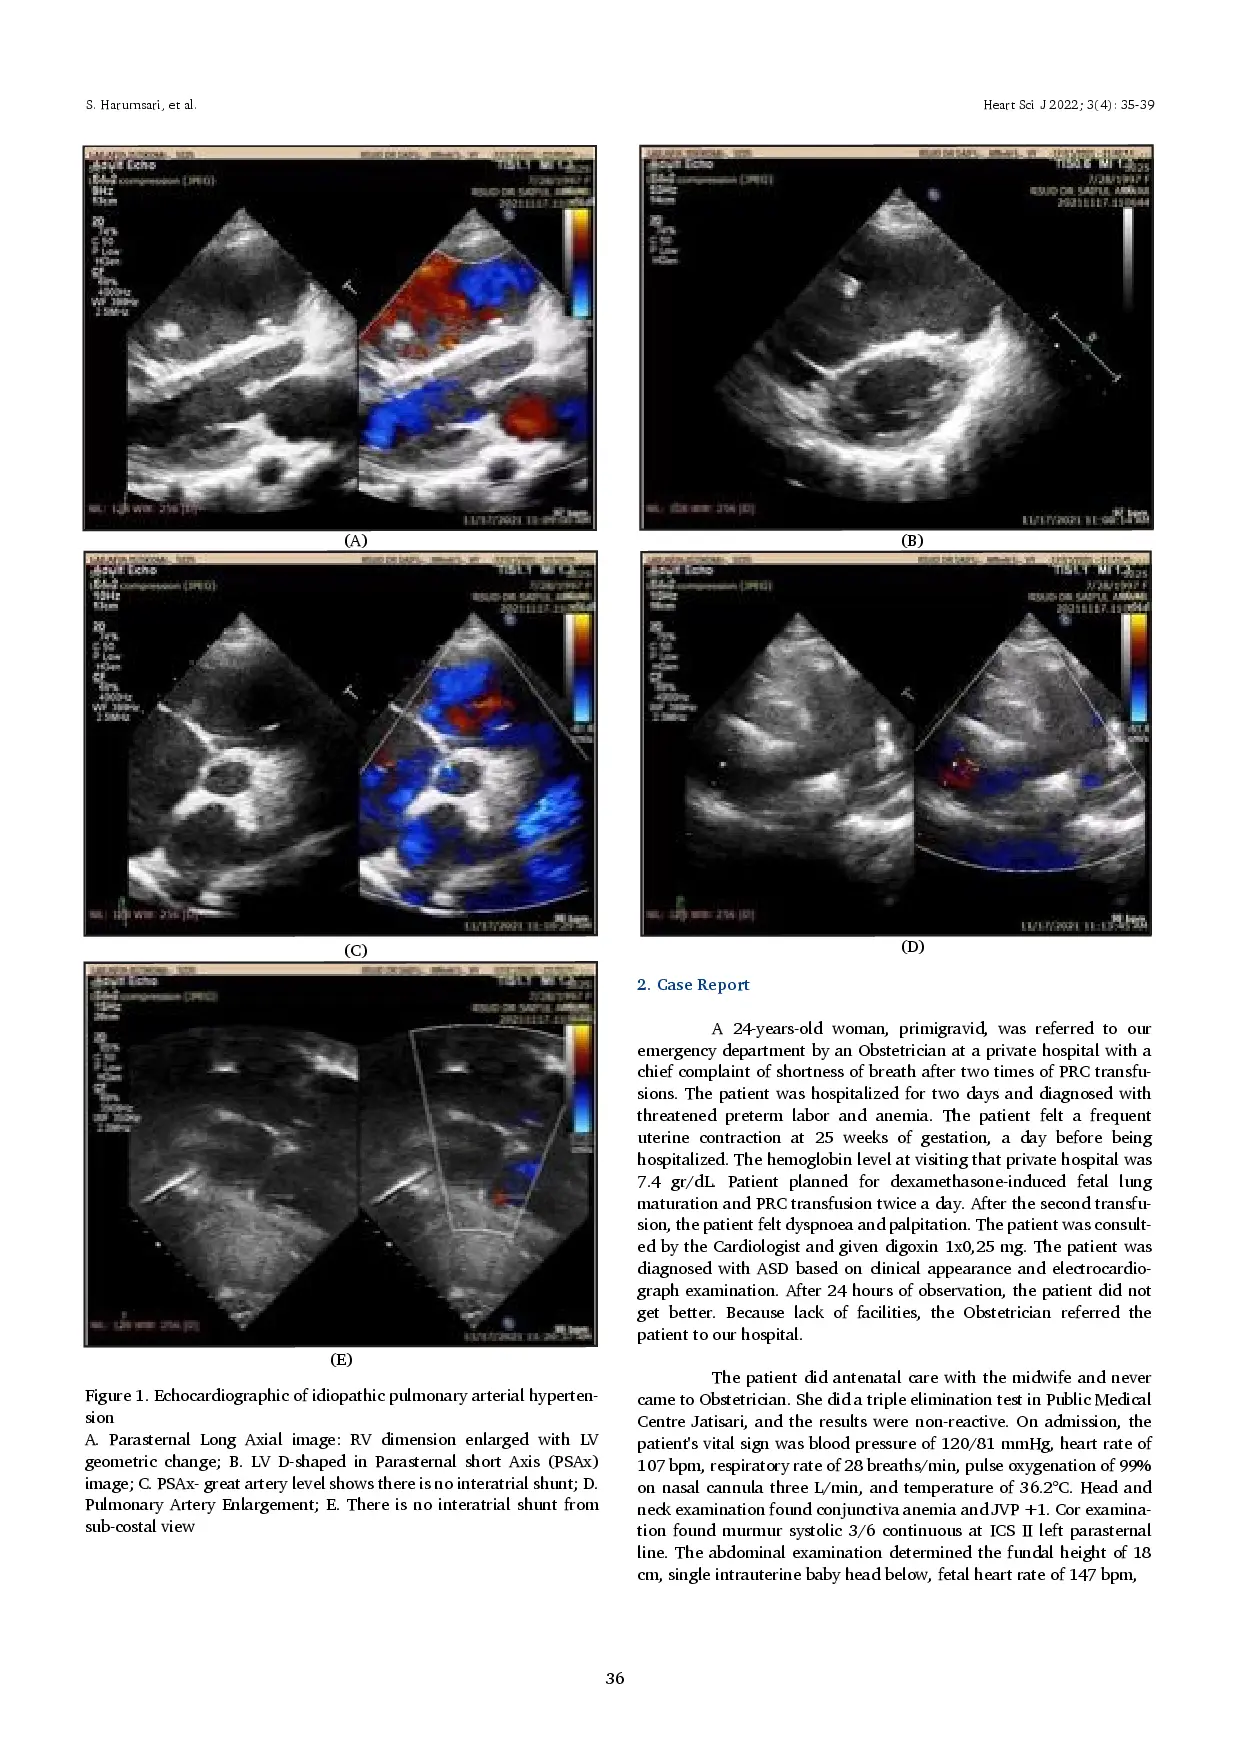

Heart Science JournalHeart Science JournalLatar Belakang: Hipertensi pulmonal (PH) merupakan gangguan kardiovaskular langka yang menyebabkan gagal jantung kanan (RHF). Meskipun sebagian besar PH terjadi sekunder akibat penyakit jantung bawaan (CHD), PH dapat terjadi secara primer akibat kelainan vaskular arteri pulmonal, yang dikenal sebagai hipertensi arteri pulmonal idiopatik (IPAH). Selain itu, perubahan fisiologis selama kehamilan dapat berpotensi memperburuk PAH dan memberikan prognosis yang buruk. Oleh karena itu, ketika ibu menolak terminasi, kehamilan dan persalinan harus dikelola oleh tim multidisiplin untuk meningkatkan hasil maternal dan fetal. Tujuan: Laporan kasus ini bertujuan untuk mendeskripsikan pentingnya diagnosis dan pengobatan dini pada PAH. Kasus: Kami melaporkan kasus seorang wanita berusia 24 tahun dengan hipertensi arteri pulmonal idiopatik (IPAH) yang baru didiagnosis pada kehamilan 25 minggu dan sebelumnya salah didiagnosis sebagai patent ductus arteriosus (PDA). Kehamilan ini disertai dengan anemia dan ancaman persalinan prematur. Sildenafil digunakan sebagai vasodilator untuk mengurangi gejala PAH. Sayangnya, kehamilan dihentikan pada 29 minggu karena PPROM setelah mempertimbangkan pemberian pematangan paru dan neuroprotektan pada janin. Pasien dipulangkan tanpa komplikasi, tetapi bayi meninggal setelah delapan hari perawatan intensif akibat HMD II yang menyebabkan gagal napas. Kesimpulan: PAH dalam kehamilan merupakan kondisi yang mengancam jiwa jika tidak diobati. Perawatan berkelanjutan dapat membantu mengendalikan gejala dan menghindari komplikasi lebih lanjut bagi ibu dan bayi.